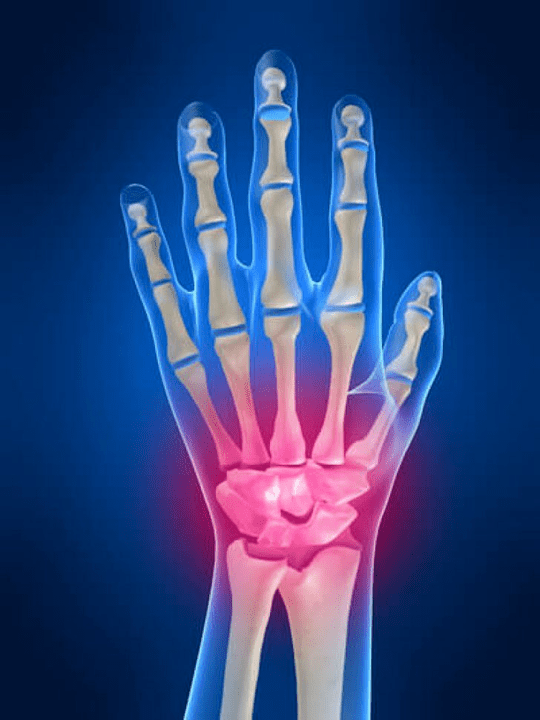

El eklemlerinin anatomisi

Elin tüm eklemleri aşağıdaki gruplara ayrılmak için alışılmıştır:

- bilek eklemi;

- bileğin eklemleri;

- karpal paten eklemleri;

- interpensiyal eklemler;

- Parlemonal-falanks eklemleri;

- İnterphalanx eklemleri.

Bilek eklemi

Bilek eklemi, proksimal kemiklerin kemikleri tarafından oluşturulur (üst) Bir dizi bilek (Trihedral, yarı -moon, skafoid kemikler) ve radyasyon ve dirsek kemiklerinin distal alanları. Dirsek kemiği doğrudan bileğin kemiklerine bağlı değildir, ancak distal (Daha düşük) eklem disk. Bu yapı, bilek ekleminin boşluğunu distal boşluktan ayırır (Daha düşük) Karo eklemi.